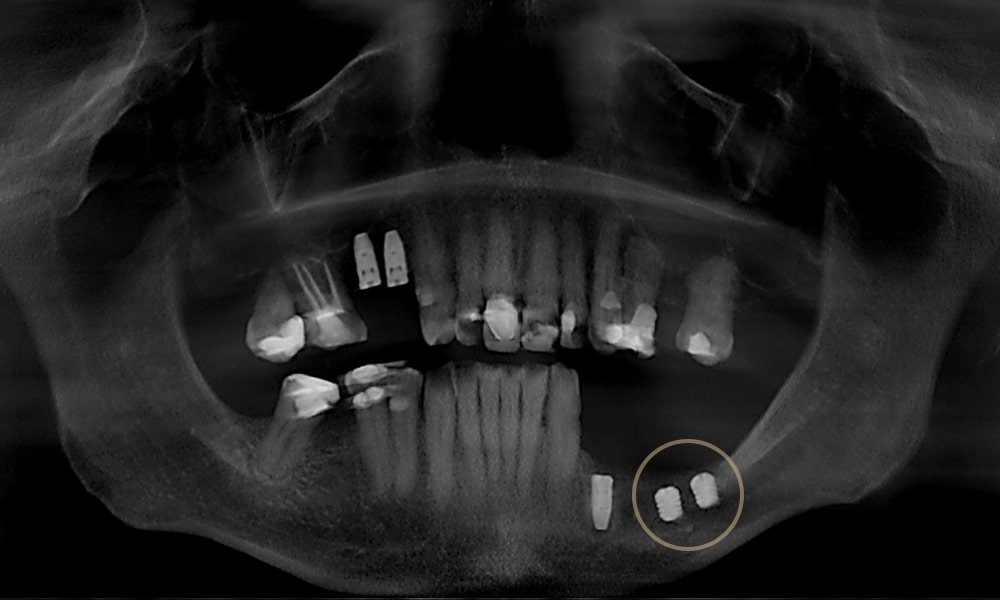

ایمپلنت های کوتاه (Short Implants) نوعی ایمپلنت دندانی با طول کمتر از ایمپلنت های مرسوم هستند. این ایمپلنت ها مخصوص بیمارانی طراحی شدهاند که ارتفاع یا تراکم استخوان فک کافی ندارند و میخواهند از جراحی های بازسازی استخوان برای کاشت ایمپلنت در ونک پرهیز کنند.

ایمپلنت کوتاه در ونک نوعی ایمپلنت دندانی است که طول آن معمولاً کمتر از ۸ میلیمتر است. در حالی که ایمپلنت های استاندارد طولی بیشتر دارند و برای کاشت آن ها به ارتفاع استخوان بیشتری نیاز است. طراحی ایمپلنت های کوتاه به گونهای است که بتوانند در شرایطی که استخوان کافی وجود ندارد، عملکردی مشابه ایمپلنت های معمولی ارائه دهند.

ایمپلنت کوتاه در ونک برای بیمارانی طراحی شده که شرایط استخوانی آنها اجازه کاشت ایمپلنت های استاندارد را نمیدهد. در واقع، این روش درمانی میتواند جایگزین مطمئن و کمتهاجمی برای جراحیهای سنگین بازسازی استخوان باشد.

وقتی استخوان فک به دلیل افزایش سن، بیماری لثه یا کشیدن دندانها تحلیل رفته باشد، ارتفاع استخوان کاهش پیدا میکند. در چنین شرایطی ایمپلنت های کوتاه بهترین گزینه برای جایگزینی دندان از دست رفته است. - جلوگیری از پیوند استخوان یا سینوس لیفت

در فک بالا و بهویژه نواحی عقب، نزدیکی به حفره سینوس معمولاً مانع از کاشت ایمپلنت استاندارد میشود. به کمک ایمپلنت کوتاه میتوان بدون نیاز به جراحی سینوس لیفت، درمان را انجام داد. - بیماران با شرایط پزشکی خاص

۱. بیمارانی با ارتفاع کم استخوان فک

افرادی که به دلیل تحلیل استخوان، ارتفاع کافی برای ایمپلنت های استاندارد ندارند، بهترین کاندیدای ایمپلنت کوتاه هستند. این افراد میتوانند بدون نیاز به پیوند استخوان درمان شوند.

۴. بیمارانی با تحلیل استخوان عقب فک بالا

در ناحیه دندانهای عقب فک بالا، نزدیکی به حفره سینوس معمولاً مانع کاشت ایمپلنت استاندارد میشود. ایمپلنت کوتاه امکان جایگزینی دندان بدون سینوس لیفت را فراهم میکند.